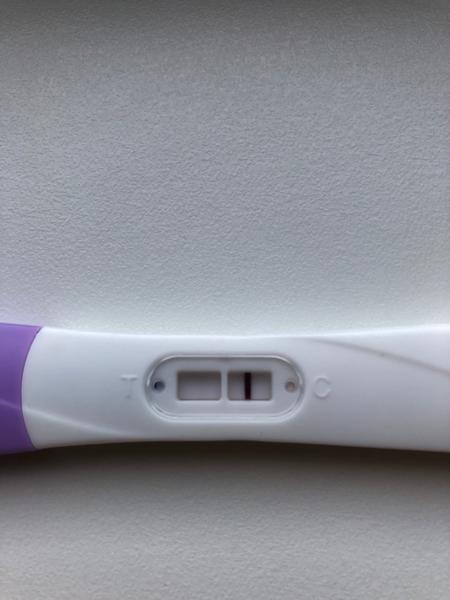

ahojte babule, mam taku otazku...mate skusenost ze pocas 3 dni vam nesilnela druha ciarka na teste ale bola rovnaka???ako duch????

@danikol dakujem, ona uz silnie, to je par tyzdnov dozadu 🙂 uz mam menej nez tyzden do kontroly u dr

Ahojte baby potrebujem radu dnes som 9-10dpo, od včera mi je zle na žalúdku, vracala som, aj dnes mi je tak isto, tak je mi cudne... A test som si spravila až teraz poobede a nič tam špeciálne nevidím vy áno? Viem ze je to skoro, ale nedalo mi tak som si test spravila a zatiaľ tam nič nie je iba taky ako duch alebo len kanálik 🤔 neviem ťažko povedať..

@tinadeville no tebe to vidno pekne, ja som to mala takto isto voľným okom to lepšie bolo vidno